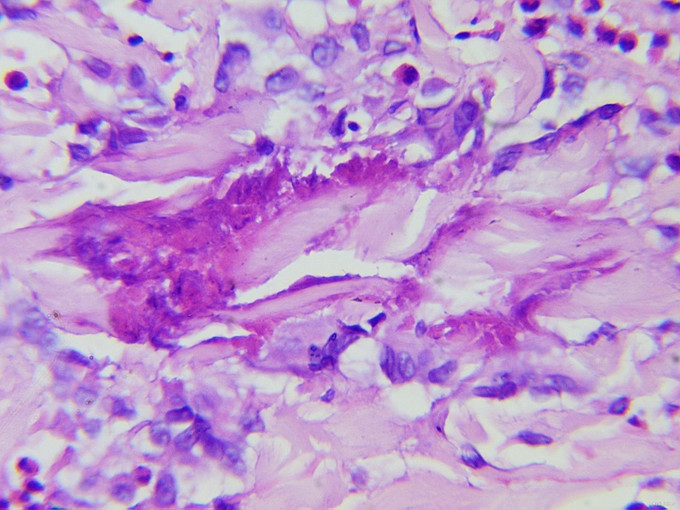

体格检查:系统检查无异常。皮肤科检查:右上肢弥漫性红肿,非可凹性,皮温高,触之较硬。双手、右前臂散在粟粒至黄豆大小水疱、大疱、脓疱,尼氏征阴性,左前臂、双足跖有少量大小不一黄色结痂面。四肢、背部、腹部多发大小不一、境界欠清之色素沉着斑。 实验室及辅助检查:血常规WBC 15.84×10*9/L,EOS% 20.4%,EOS 3.88×10*9/L 。疱液细菌培养及真菌培养均未见异常。ANA、dsDNA,、ENA谱均阴性。组织病理检查:表皮棘层不规则肥厚,皮突延长,真皮乳头高度水肿,真皮全层和皮下脂肪可见大量嗜酸性细胞浸润,并可见火焰现象。

嗜酸性蜂窝织炎(Eosinophilic Cellulitis)是一种以反复发作的红色水肿性斑块为特点的疾病,最早由Wells于1971年首先报告,又称Wells综合征(Wells syndrome)。本病发病无性别差异,患者年龄跨度大,平均37岁。疾病在发病早期类似于急性蜂窝织炎,皮肤病理表现为显著的炎症性肉芽肿特征。皮损好发于四肢和躯干。常表现为边界清晰、水肿性、触之坚实的环状红色斑块,类似蜂窝组织样,但也可有其他多种临床表现,包括水疱、结节、丘疱疹和瘙痒性剥脱性炎性丘疹。有些患者可引起疼痛和瘙痒,皮损愈后不留瘢痕。 本病病理变化:急性期皮损活检可见真皮水钟,并有大量的嗜酸性粒细胞浸润,表皮下偶见水疱。亚急性期真皮有弥漫性组织细胞和嗜酸性粒细胞浸润,部分碎裂的嗜酸性粒细胞围绕着坏死的胶原纤维形成斑块状浸润,可以见到大而淡染的组织细胞及异形巨细胞围绕嗜酸性不定形物呈栅栏状排列的“火焰像”。消退期组织细胞渐进性坏死,类似肉芽肿的改变,仍有“火焰像”持续存在。根据患者的临床特征及病理上“火焰像”的特点可诊断本病。本例患者起病时皮疹不典型,开始时为单侧发病,表现为红色小丘疹、后逐渐形成水疱、大疱,故曾被诊断为“带状疱疹”,皮损进展到对侧上肢并出现脓疱后又被诊断为“掌跖脓疱病”,最终取皮肤病理而确诊。 本病发病原因的机制尚不清楚。部分患者血清中可以出现抗核抗体,组织病理上可见广泛发生的纤维蛋白样坏死,小血管炎及嗜酸性粒细胞增多,故认为可能为自身免疫性疾病,本病是否是原发性独特的疾病还是对其他可能的过敏刺激的反应还不清楚。它与昆虫叮咬、盘丝虫病、肠道寄生虫病、水痘、腮腺炎、破伤风疫苗接种、药物反应、骨髓增生症、特应性素质、嗜酸性粒细胞增多综合征和真菌感染有关。 本病对抗生素治疗无反应,该患者曾使用“头孢类抗生素”治疗无效也印证该点。有效的治疗包括口服抗组胺药、氨苯砜或小剂量激素,UVB或PUVA也可能有效。本患者经小剂量激素治疗后病情有改善,目前仍在随访中。